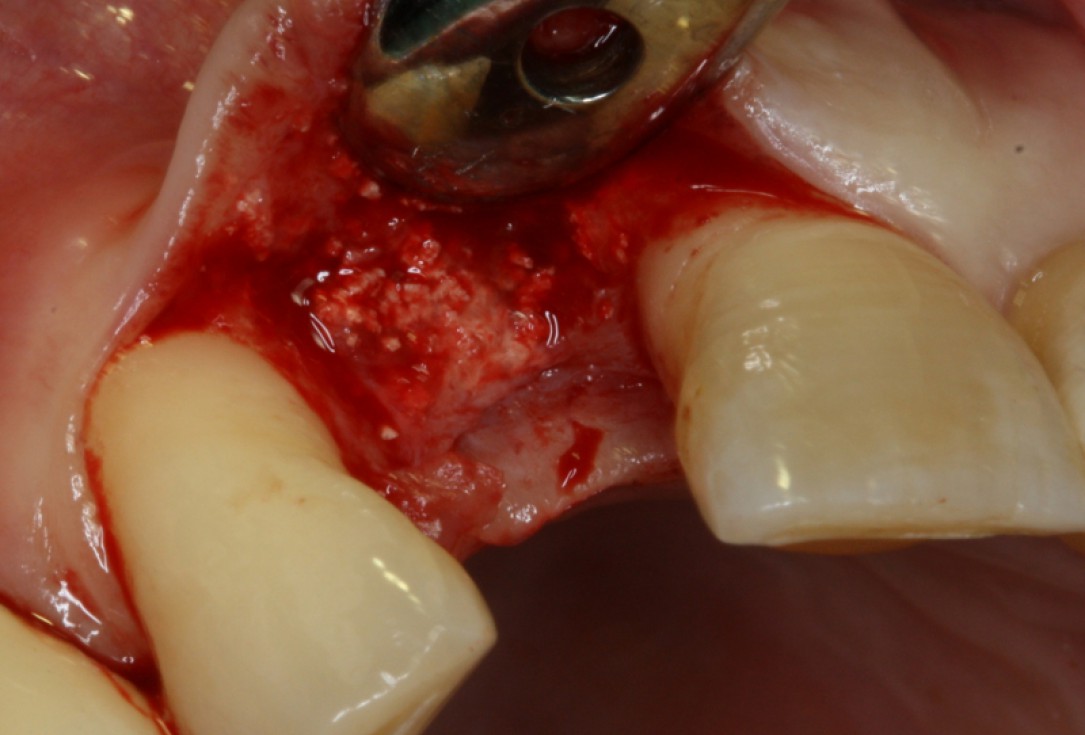

08/20 - Surgical presentation of the alveolar ridgeGBR with maxresorb® & Jason® membrane - Prof. Dr. Dr. D. Rothamel